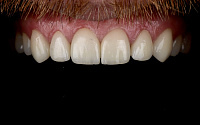

Функциональность и эстетика. Зубы сохраняют свою жевательную функцию и красивый контур улыбки, что особенно важно для передних зубов.

Наши работы